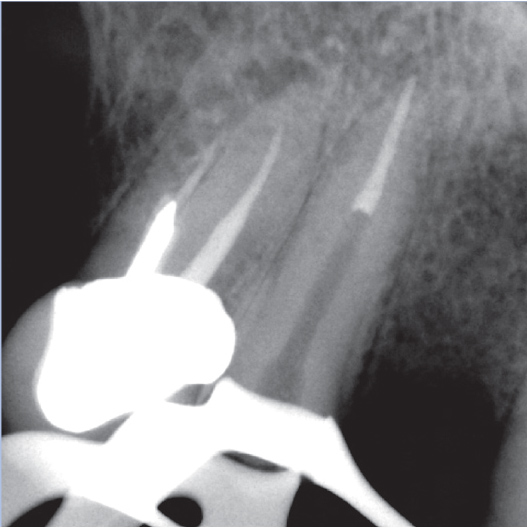

After

After Root Canal treatment